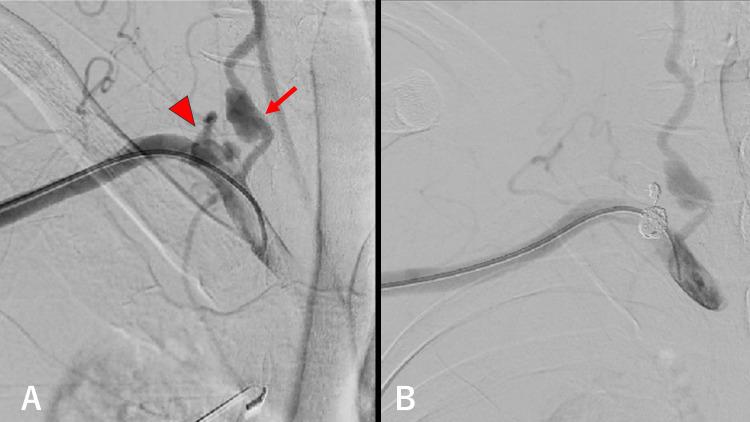

Neurofibromatosis type 1 (NF-1) is associated with vascular complications, including stenosis or the occlusion of the abdominal aorta and renal arteries. However, reports on the occurrence of extracranial vertebral artery aneurysms are scarce. A man in his 40s had back pain and was feeling unwell. Contrast-enhanced computed tomography revealed a right hemothorax and aneurysms involving the right thyrocervical trunk and at the right vertebral arterial origin. The patient was successfully treated with endovascular embolization and achieved a full recovery. Notably, extracranial vertebral artery aneurysms tend to be detected at a later age compared to other complications such as optic gliomas of NF-1, and endovascular treatment has proven effective for managing these aneurysms.

1型神经纤维瘤病(NF-1)与血管并发症相关,包括腹主动脉和肾动脉狭窄或闭塞。然而,关于颅外椎动脉动脉瘤发生情况的报道很少。一名40多岁的男性出现背痛且感觉不适。增强计算机断层扫描显示右侧血胸以及累及右侧甲状腺颈干和右侧椎动脉起始处的动脉瘤。该患者通过血管内栓塞治疗成功治愈并完全康复。值得注意的是,与NF-1的其他并发症如视神经胶质瘤相比,颅外椎动脉动脉瘤往往在较晚的年龄被发现,并且血管内治疗已被证明对处理这些动脉瘤有效。